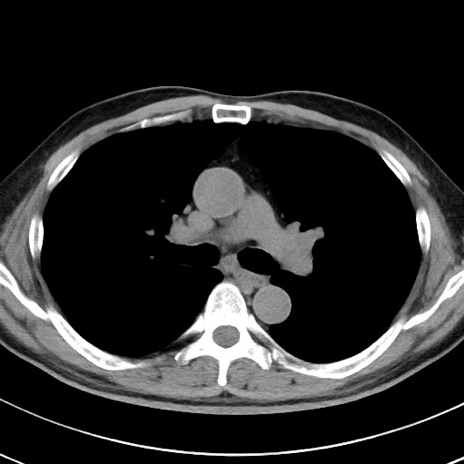

【腹部TIPS】症例29 参考症例 CT(横断像)

症例

70歳代男性